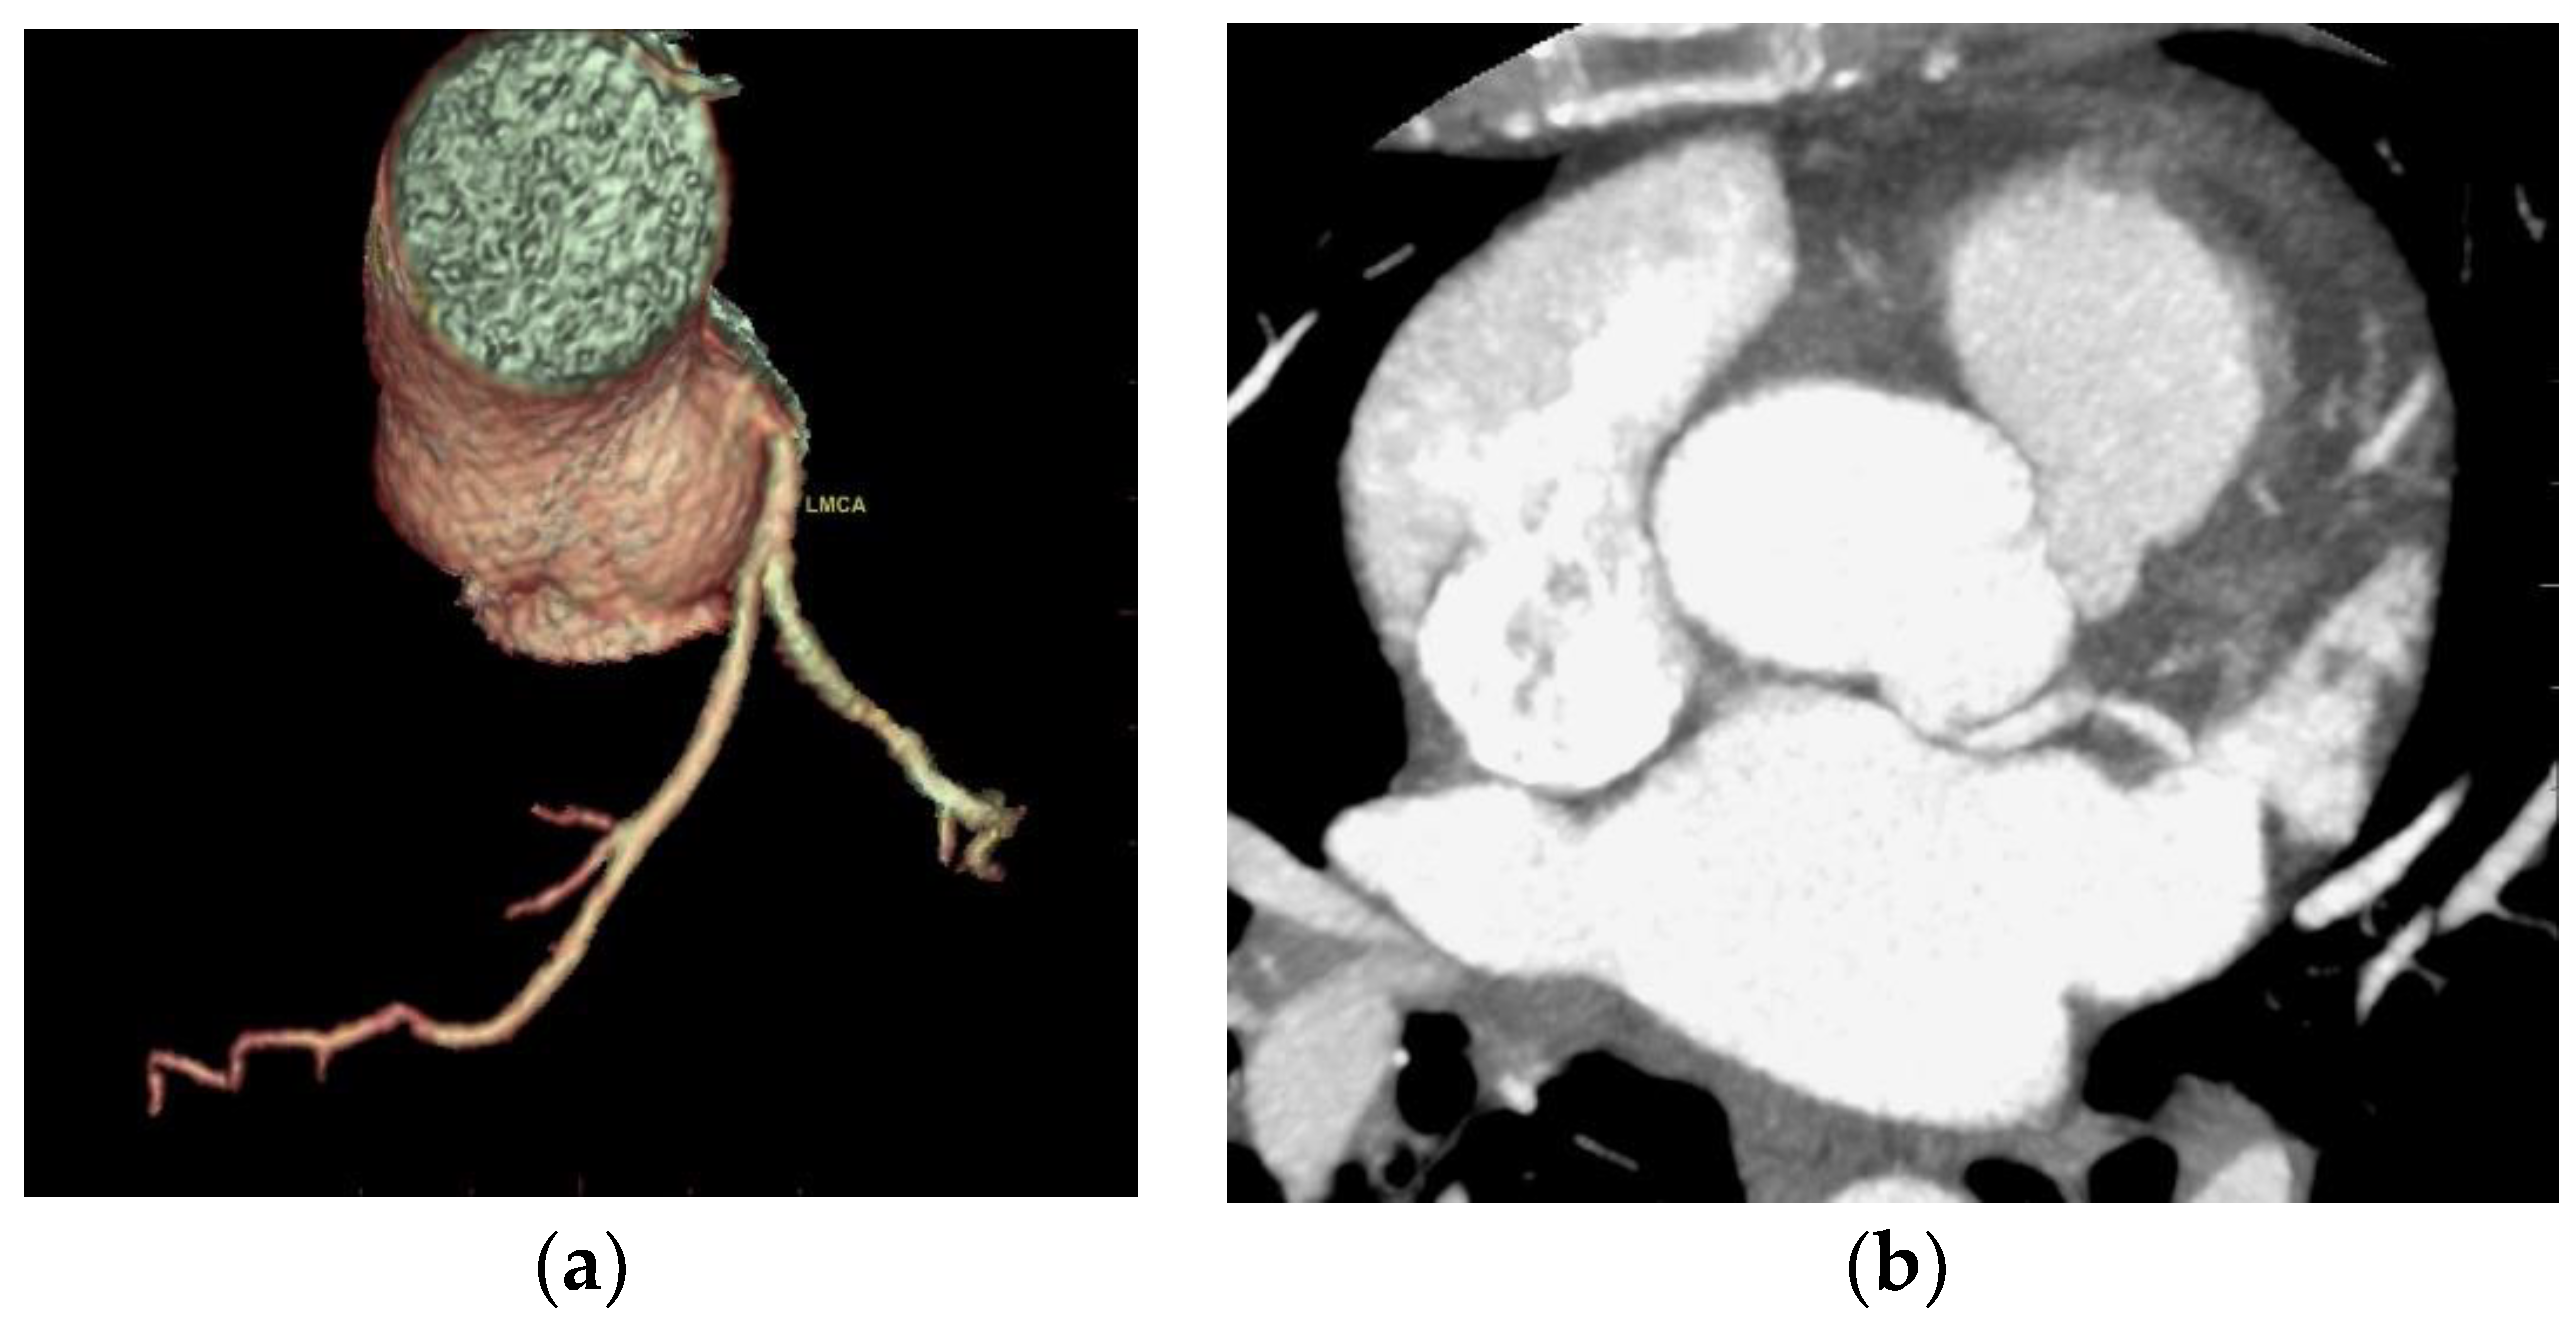

One case of detachment of the left main coronary artery from the left coronary sinus at an acute angle was found (

Figure 4).

One anomaly of detachment of the left main coronary artery from the left coronary sinus at an acute angle was encountered. In terms of route, the normal proximal orientation of the LM and RCA is 45° to 90° to the aortic wall, with a subepicardial extramural route to destination [

5]. In scientific literature, the prevalence of acute angles of detachment of the coronary artery from the coronary sinus is 2% [

2].